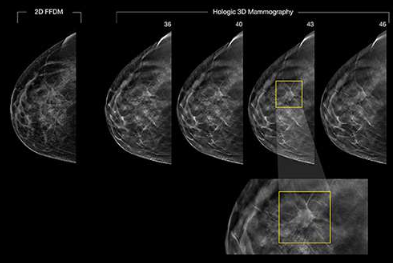

Automatização da detecção de câncer de mama com análise de mamografias e dados clínicos.

Desenvolvimento de um algoritmo capaz de classificar a qualidade do posicionamento de exames de mamografia.